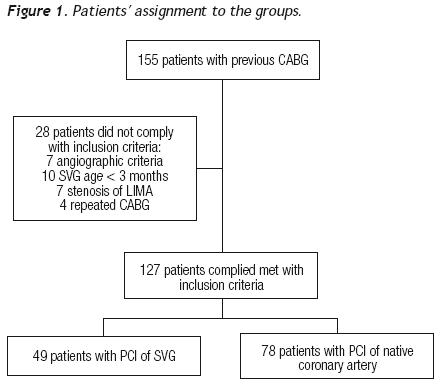

From January 1998 to December 2007, 155 PCIs were performed in patients with a history of coronary revascularization surgery. Seven patients were excluded based on angiographic criteria (total occlusion, intra–stent restenosis, or combined treatment), as well as 21 more due to age of the venous graft < 3 months (n = 10), stenosis of the internal mammary artery (n = 7), and four patients with repeated surgical treatment. Of the 127 patients fulfilling the inclusion criteria, 49 were subjected to percutaneous intervention of the saphenous vein (Group 1) and 78 to PCI of the native vessels (Group 2). Figure 1 describes patients' assignment.